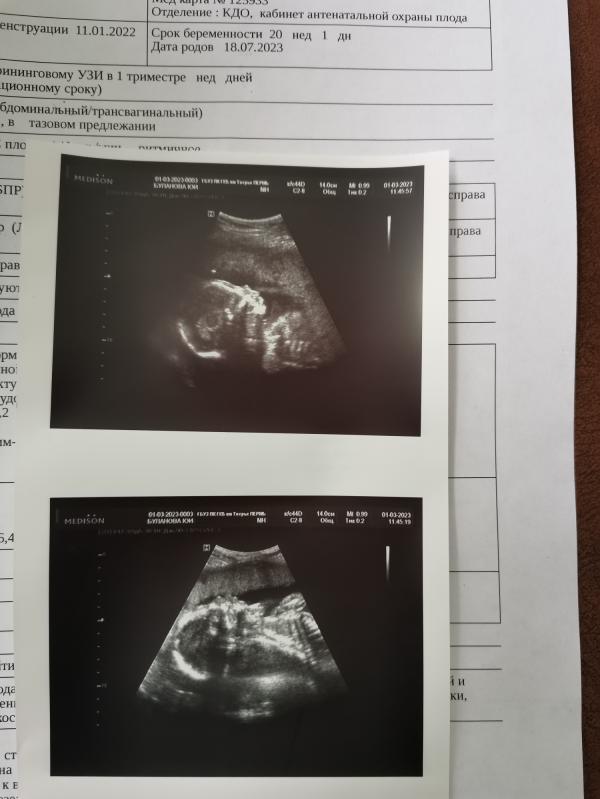

Экватор 🤩пройден второй скрининг, мы снова ждём мальчика💙как это принять пока не знаю, но главное все хорошо 🤞🙏

Тоже сегодня экватор😊 в пятницу на второй скрининг)